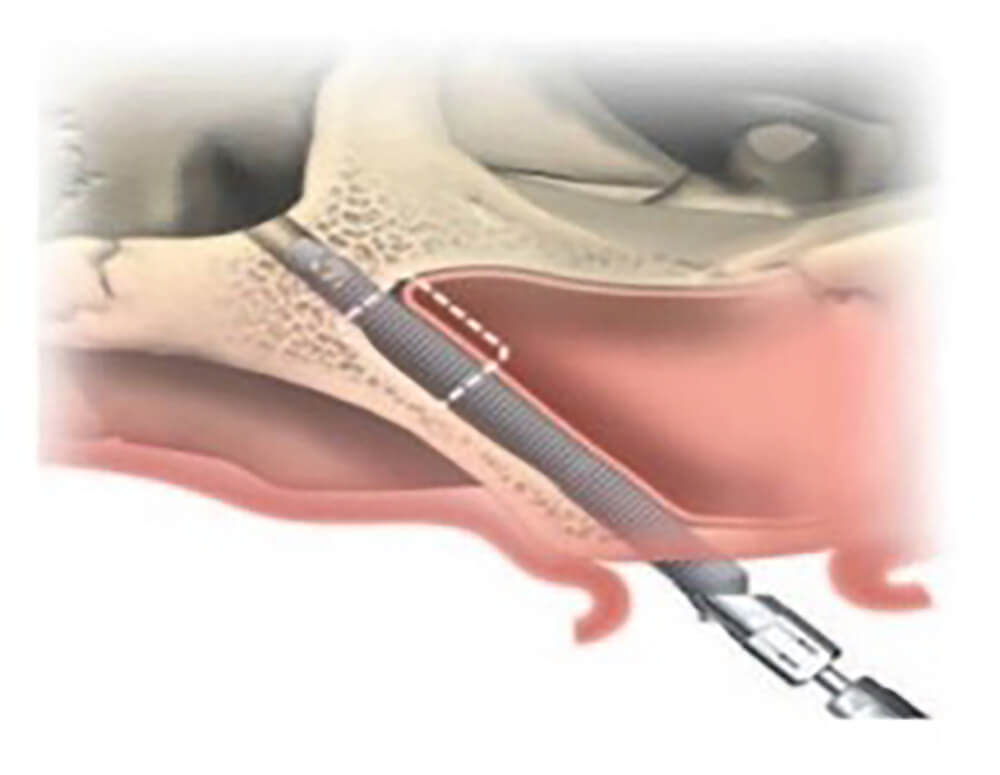

顴骨是顏面主要支架,骨質密度高且強壯,不易隨著時間流失,足以提供植體良好穩定性。一般植體的長度約在 8 到 13 毫米左右,而顴骨植體的長度一般會超過 35 毫米,甚至達到50毫米,透過更長更強壯的植體,跨過萎縮骨質區,以顴骨固定植體,使上顎骨基底喪失的患者也能獲得妥善治療。